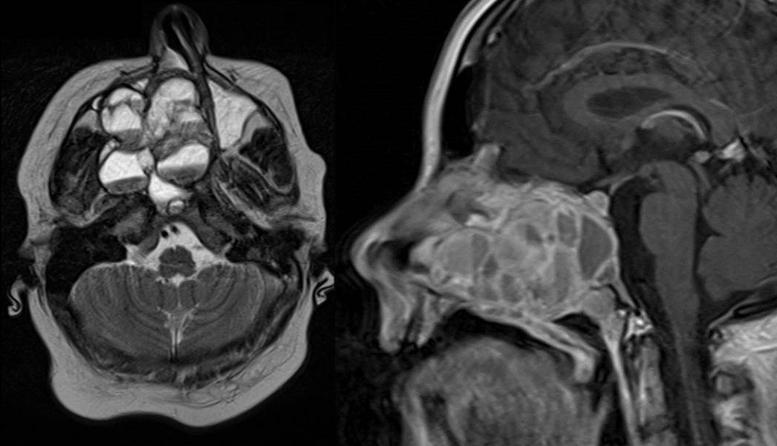

Endoscopic surgery of an extensive aneurysmatic bone cyst of the paranasal sinuses in a 12-year-old patient.

Braz J Otorhinolaryngol. 2019 Nov-Dec;85(6):803-808. doi: 10.1016/j.bjorl.2016.04.008. Epub 2016 May 6.

https://cdn.ncbi.nlm.nih.gov/pmc/blobs/dc25/9443026/37bdcf821937/gr1.jpg